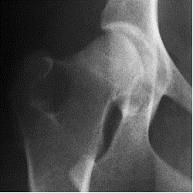

當前主流的骨關節保健品主要有葡萄糖胺(glucosamine)、軟骨素(chondroitin),以及有機硫同化物(methyl-sulfonyl-methane,即MSM)等。葡萄糖胺和軟骨素在骨關節處形成蛋白聚糖,吸收水分和體液,使關節運動時得到潤滑,而MSM則是止痛劑。這些都僅僅是緩解症狀,很難治本。美國UCLA骨科專家臨床研究表明,一般葡萄糖胺要四、五年才能修復軟骨;而以II型骨膠質(kolla2)為主方,輔以上葡萄糖胺、MSM等,則大大縮短消除關節疼痛和修復軟骨的時間。研究證明服用II型骨膠質(kolla2)六周后,患有髖關節發育異常的犬科動物恢復了正常運動功能,隨後的X-射線檢查表明其髖關節軟骨恢復正常。

服用骨膠質Kolla2之前

服用骨膠質Kolla2之後一些非類固醇類消炎藥物如喜樂保(celebrex)和威克適(vioxx)曾被廣泛使用於骨折病人和骨關節炎病患,使其減少關節疼痛。而2004年以來,越來越多的研究發現這些藥物除了止痛之外並不能改善病人的骨骼健康,反而加長了骨折恢復期,並增加腦中風、心臟病發作的危險。2005年4月,美國FDA勒令以上各種藥物下櫃。II型骨膠質(kolla2)完全不含任何西藥止痛藥成份,2005年上市以來,迄今沒有發現任何一例毒副作用報告。